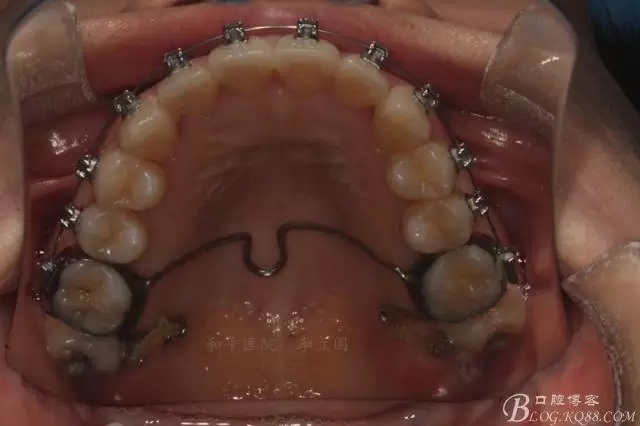

該病例主要為17、27頰側(cè)位同時伴有伸長,當然種植支抗可以解決,但還有簡單實用的辦法嗎?如圖,在橫腭桿遠中延伸出牽引鉤,位置盡量遠離合平面,7粘舌側(cè)扣,牽引力的方向為壓低及舌向,下圖為兩個月的效果,17已到位,27還未到位。